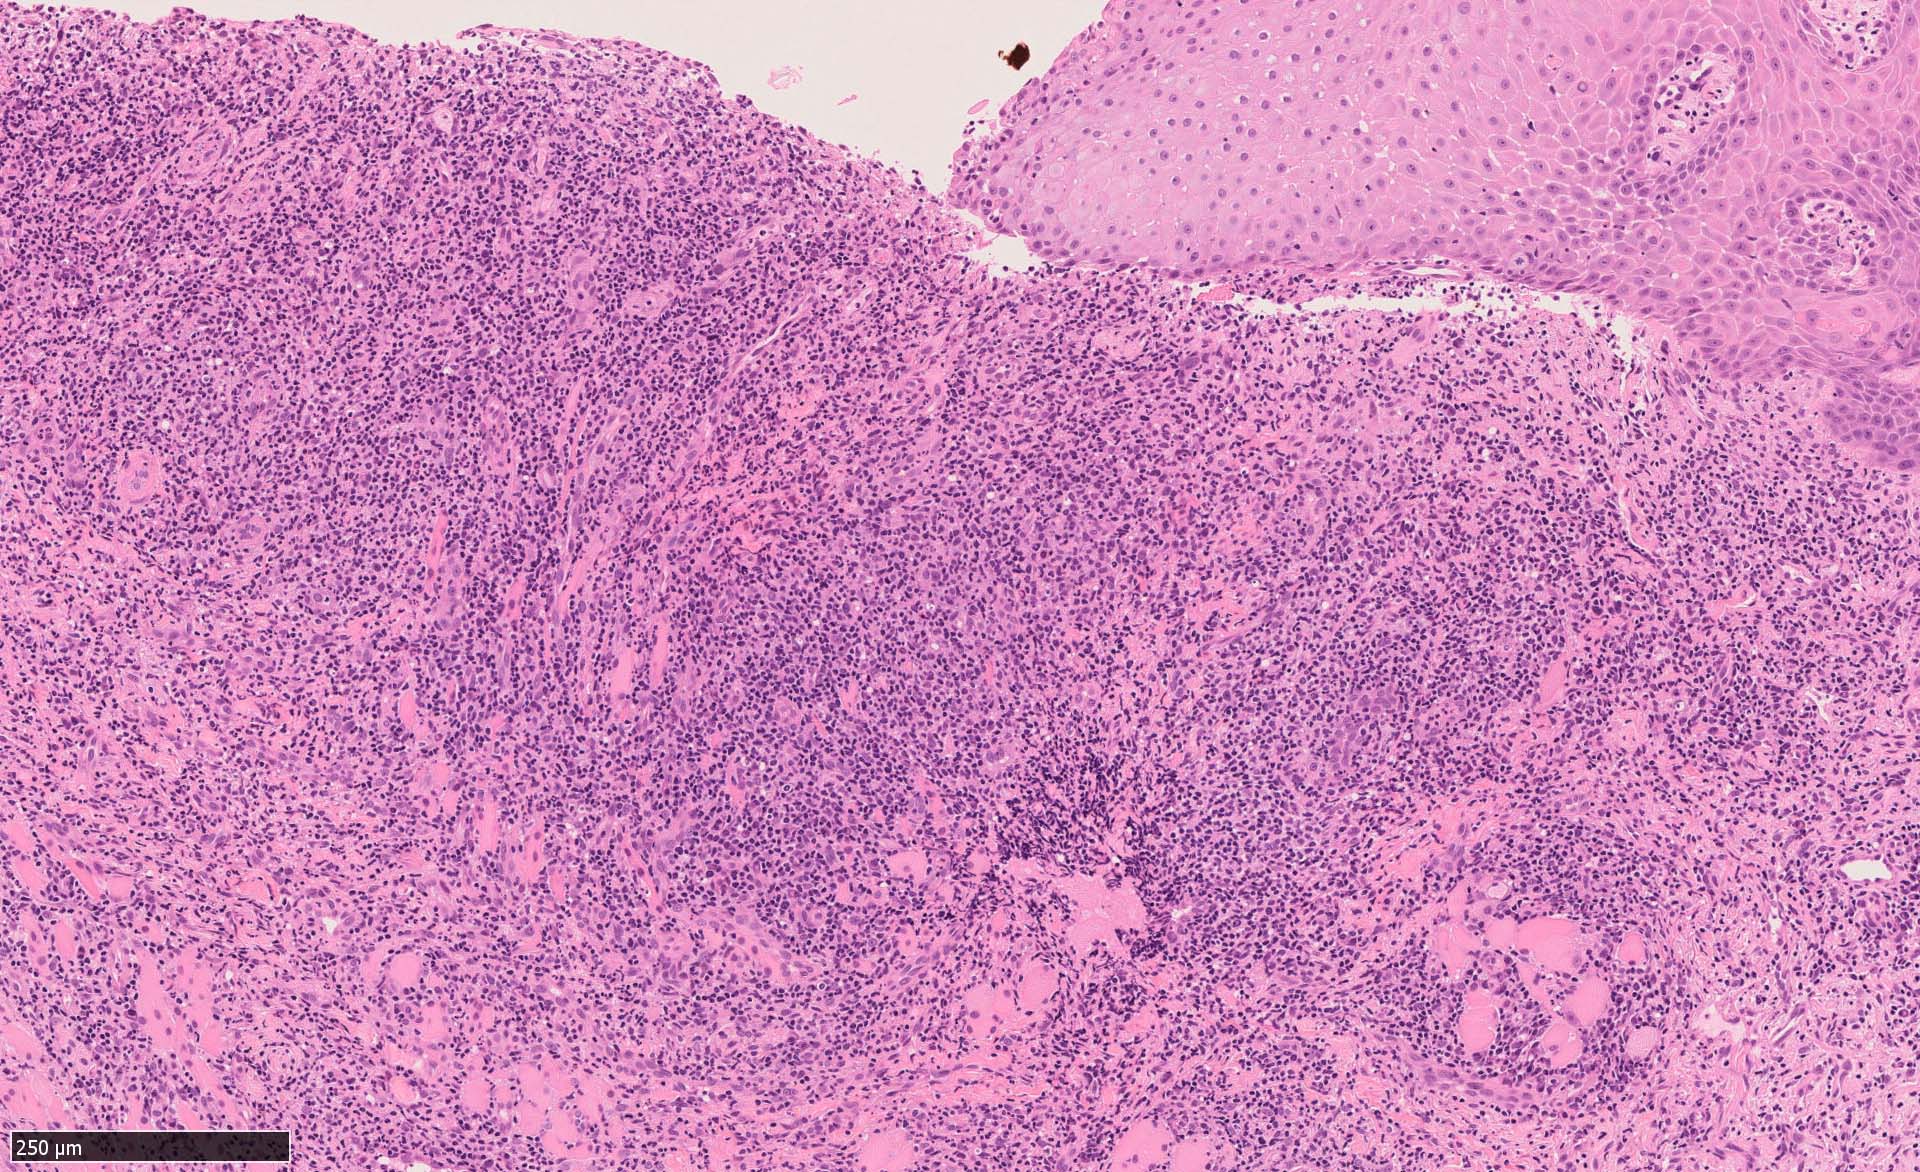

EBV陽性粘膜皮膚潰瘍(EBVMCU)は、EBV陽性の異型大型B細胞および/またはHodgkin/ Reed-Sternberg (HRS)様細胞を含む多形リンパ球浸潤を伴うリンパ増殖性疾患(pleomorphic pattern)で、

典型的には免疫不全/調節障害を有する患者の粘膜および皮膚に発現する。--WHO 5th classificationに記述された定義